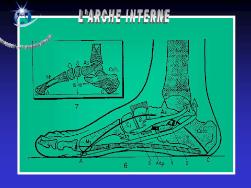

Anatomie du pied

Le squelette du pied est composé de 28 os qui se combinent en de nombreuses articulations.